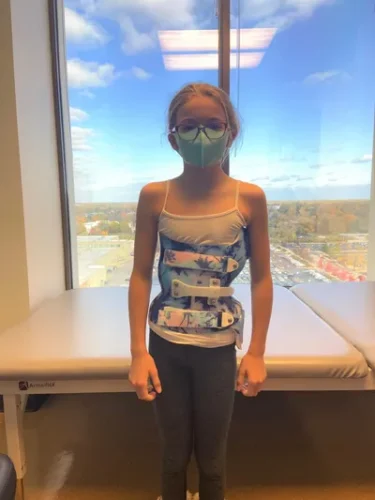

يُعد الحزام الطبي أحد أكثر الطرق فعالية لعلاج اعوجاج العمود الفقري عند المراهقين ومنع تفاقم الانحناء خلال مرحلة النمو. ومع اقتراب انتهاء فترة العلاج، يتساءل الكثير من الأهل: ماذا يحدث بعد إزالة الحزام؟ هل سيعود الانحناء؟ وكيف يمكن متابعة الحالة والحفاظ على النتائج؟ هذا المقال يقدّم إجابات مفصلة بطريقة سهلة الفهم للأهل، مع التركيز على الوقاية والمتابعة بعد التوقف عن الحزام.

نجاح الحزام الطبي لعلاج اعوجاج العمود الفقري عند المراهقين لا يعتمد على ارتدائه فقط، بل على تفاصيل دقيقة مثل تصحيح دوران الفقرات الأولى وسرعة هذا التصحيح. متابعة الأهل مع الطبيب، الالتزام بعدد ساعات الارتداء، واستخدام الحزام المصمم خصيصًا لكل طفل، جميعها عوامل تزيد من فعالية العلاج وتمنح الطفل فرصة أفضل لنمو ظهر مستقيم وحياة طبيعية.

التطور الكبير في تصميم الأحزمة الطبية جعل علاج اعوجاج العمود الفقري عند المراهقين أكثر نجاحًا وأقل إزعاجًا. باستخدام تقنيات التصوير الثلاثي الأبعاد والمحاكاة الرقمية، أصبح الحزام أكثر خفة وراحة، ويعطي نتائج أفضل في تصحيح الانحناء والتواء العمود الفقري.

ارتداء الحزام العلاجي لعلاج اعوجاج العمود الفقري ليس مجرد إجراء بسيط، بل هو التزام يومي يؤثر على مسار العلاج بالكامل. ويجب الاهتمام بعدد ساعات الارتداء، ودرجة الإحكام، والمتابعة الدورية. تذكّر دائمًا أن الالتزام الحقيقي هو ما يصنع الفرق بين التقدم الملحوظ والثبات أو التراجع في الحالة.

- الالتزام بارتداء الحزام: يجب ارتداء الحزام وفقًا لتعليمات الطبيب لتحقيق أفضل النتائج.

- راحة استثنائية: يتميز حزام PioBrace بتصميمه الذي يوفر أقصى درجات الراحة للأطفال طوال فترة العلاج.

- سهولة الاستخدام: يمكن ارتداؤه لفترات طويلة دون التسبب في أي إزعاج للأطفال.